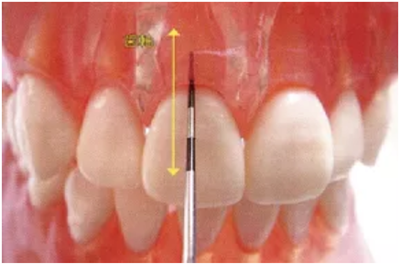

4、讀取探針的數(shù)值

探針的刻度是以1mm為單位來讀取的。但是在臨床上偶爾也會(huì)有不確定的情況發(fā)生。

不確定的情況下為了不遺漏問題,建議記錄下高的數(shù)值。

● 探診數(shù)值的讀取方法

只有6mm

記錄數(shù)值為7mm

記錄數(shù)值為4mm